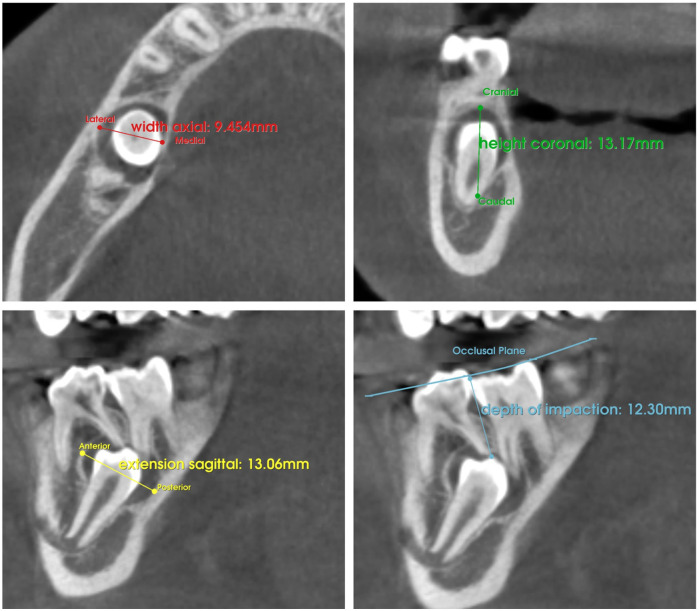

Methods: The sample size consisted of 22 impacted teeth divided into two groups: with odontogenic lesions (Group IwL) and without lesions (Group IwoL). Pre- and post-treatment radiographs, taken before and after conservative surgical or orthodontic-surgical management of impacted teeth, were used to assess the occurrence of dilaceration in both groups. Fisher's exact text was applied to compare the prevalence of dilaceration in both groups. In order to analyze the influence of each additional variable on dilaceration, a multivariate analysis was performed through logistic regression.

Results: Root dilaceration was significantly more common in Group IwL (72.73%) than in Group IwoL (18.18%) (p = 0.030). No significant association was found between root dilaceration and additional variables, including impaction depth, cortical bone contact, maximum lesion size, and lesion volume.